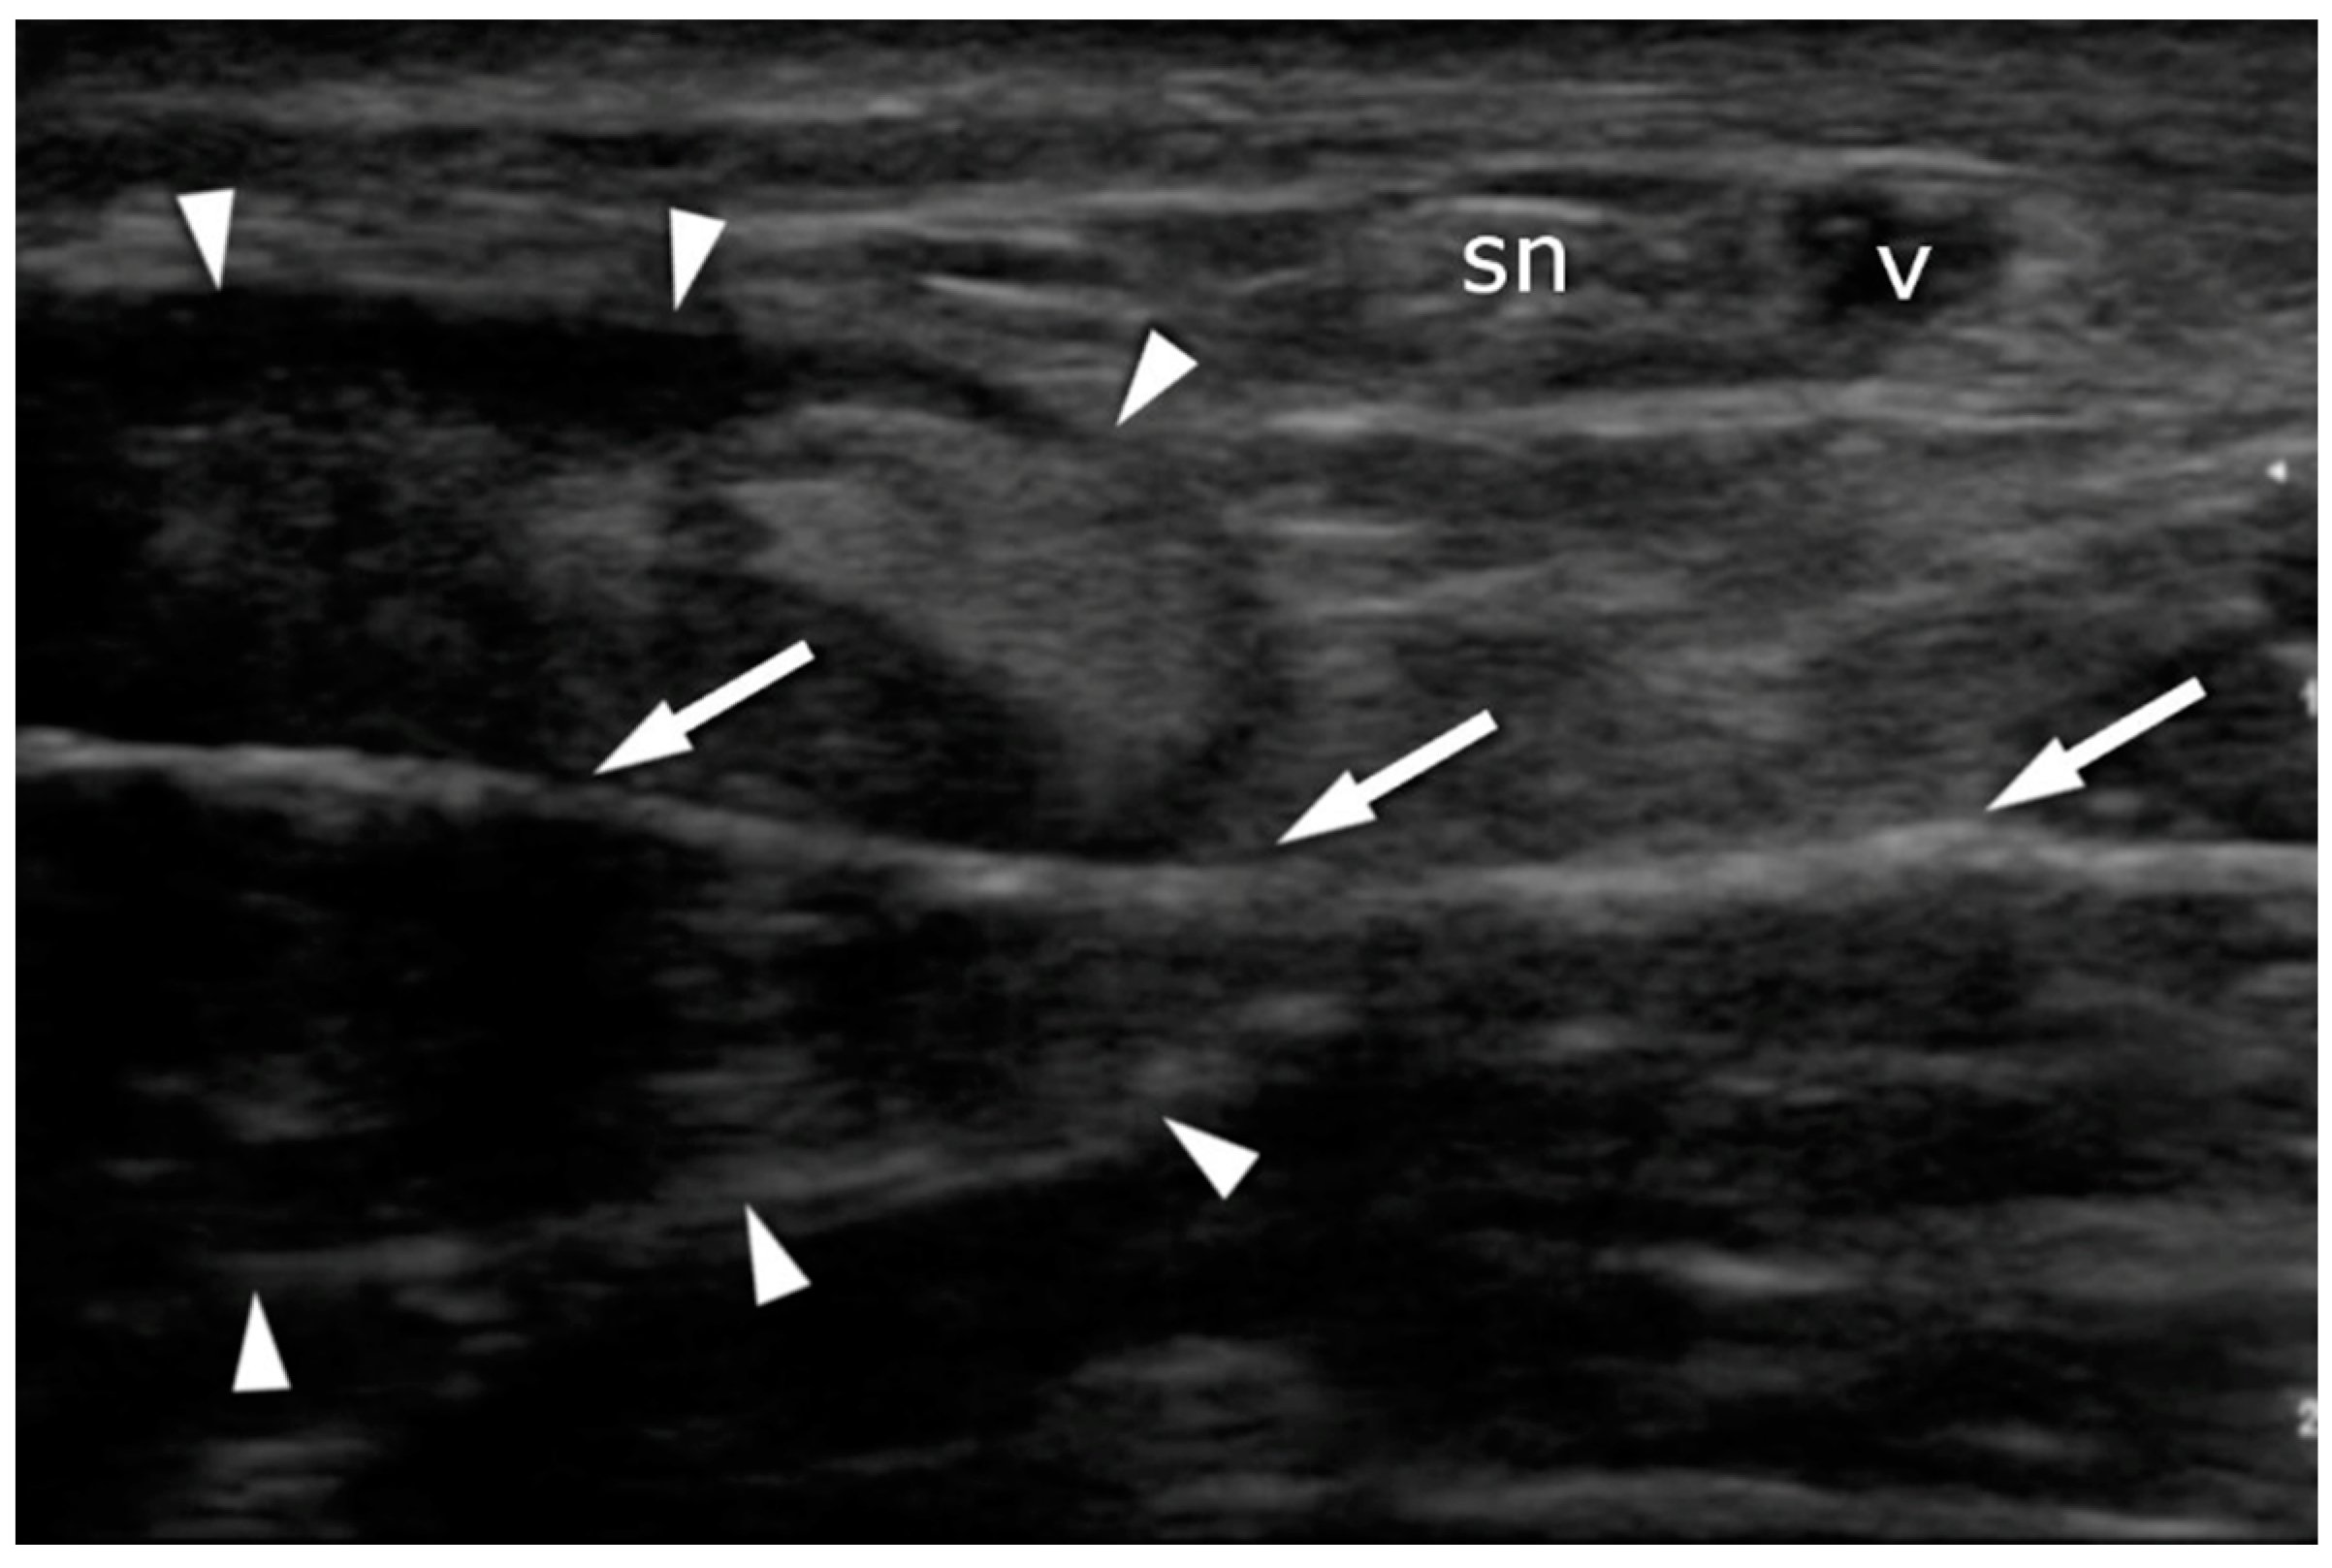

A high-resolution real-time ultrasound examination was performed in the operation room. We used a sterile draped high-frequency (10–12 MHz) linear probe. Transverse scans were used to localize the SN. It was followed from the proximal area of the calf—where it laterally follows the saphenous vein in its fascial compartment between the two heads of the gastrocnemius—to the distal area and the lateral malleolus area. The SN’s echogenicity is oval and typical of nerves, showing hyperechogenic spots in the hypoechogenic area surrounded by the hyperechogenic sheath (Figure 5, Supplementary Material Video S1). The entry point and the angle of the needle were chosen with direct US guidance (Figure 6, Supplementary Material Video S2). The suture course was checked before it entered the skin incision (Figure 7, Supplementary Material Video S3).

Figure 7.

Achilles tendon (arrowheads) after suture deployment: transverse plane. Note that the suture placement (arrows) avoids contact with the sural nerve (sn) and the vein (v).